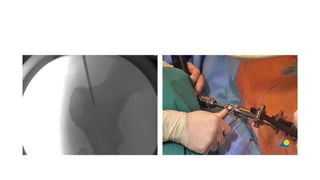

• Antegrade nailing approach

with piriformis entry point

MIO approach to the subtrochanteric region

Skin incision

• The lateral proximal incision

starts at the greater trochanter

and continues distally as far as

needed.